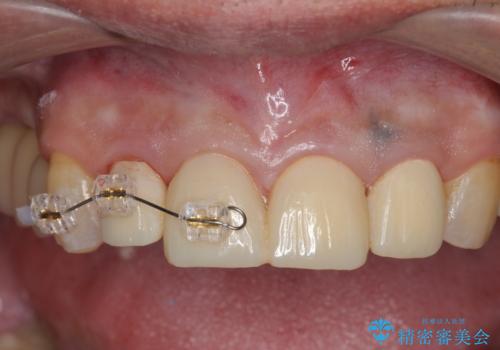

インプラント治療・セラミック治療を含む 全顎的虫歯治療

- 「 仕事が忙しく、虫歯を放置しすぎてしまった。この際全てきっちりと治したい。」と来院されました。

以上のような問題を、徹底的な虫歯治療、歯周外科、インプラント治療、部分矯正治療、精密根管治療を用いてひとつずつ解決ししっかりと長期的に食事を楽しめるような口腔内環境の再構築を目指します。